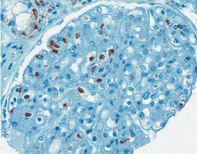

Our kidney program uses microarray analysis of transcriptional changes as a tool to improve diagnosis and to understand the pathogenesis of various human diseases including allograft rejection.

A major focus has been to define the markers that differentiate T cell-mediated rejection (TCMR) from antibody-mediated rejection (ABMR) - please see The ATAGC histology regression equations and Reference Standard classification for kidney transplant biopsies. This is significant because these events require different treatment strategies, resulting in different treatment responses and graft outcomes.

Using the knowledge we generate with microarrays in concert with the clinical information and outcomes we obtain by tracking kidney transplant patients over time, we can reclassify the information in the biopsy, and improve diagnostic accuracy. We are establishing a new diagnostic system for defining the disease states in kidney transplants in order to understand, prevent, and treat the diseases that cause graft failure - please see the Molecular Microscope® System (MMDx).